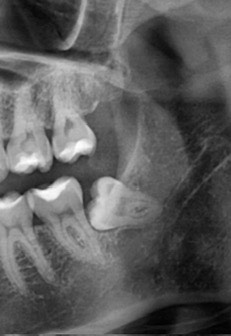

Мамочки (особенно, кто еще не решился или боится),хочу поделиться хорошим опытом по удалению сложного зуба мудрости. По омс нужно сдавать много анализов и ложится в стационар на 3 дня! У меня нет такой возможности, а зуб нужно убирать. Он двигает и давит на соседние зубы, также может развиться кариес, как у этого,так и у соседнего из-за неправильного расположения. А это уже другие сложности и деньги тоже. В стоматологии Оникс такой прекрасный хирург (молодая женщина). С ней было очень комфортно,...